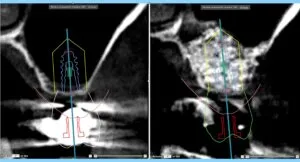

このような場合、上顎側壁よりアプローチを行なって、上顎洞内を底上げし、骨を造り上げる手術を行います。これが上顎洞挙上術です、昨年の12月に2例行い、この4月に評価を行いました。上顎洞内には、骨を造る骨芽細胞が多く存在し、組織工学に則って、①細胞、②成長因子、③骨補填材を配合し、組み合わせた生体材料を補填するのです。

当医院では、PRGF(成長因子)を使用します。これが重要です。PRGFを使用すると、未使用より約1.5倍創傷治癒が速まり、25%ボリュームが増大します。つまり通常は骨になるまで6ヶ月を要しますが、PRGFを使用すると、4ヶ月で造骨しインプラント埋入術が可能です。